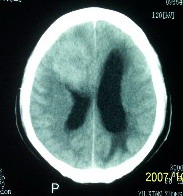

f    29岁   头闷  头晕1月余

肿瘤累及颅底前颅窝,部分层面见散在钙化,中心坏死。支持:脑膜瘤!

肿瘤长入侧脑室,侧脑室明显扩大, 病灶边界清楚,其内可见低密度坏死区,中枢神经细胞瘤?室管膜瘤?

镰旁高密度灶,中间低密度坏死区,周围水肿较轻,支持脑膜瘤诊断,建议结合增强扫描。

右额叶底部巨大等低混杂密度肿块,边界清楚,周围水肿轻度,明显占位效应。蝶鞍扩大,部分骨质破坏。

考虑脑膜瘤,建议增强扫描进一步检查。

蝶鞍受压吸收,可以排除室管膜瘤。肿瘤最大层面不在蝶鞍可以排除垂体瘤。支持脑膜瘤